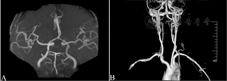

T2加权成像(A)和液体衰减反转恢复序列(B)可见左侧小脑半球存在点状高信号,弥散加权成像(C)呈明显高信号;T2加权成像(D)和液体衰减反转恢复序列(E)疑见左侧延髓背外侧点条状高信号,弥散加权成像(F)呈明显高信号

本例患者急性起病,以四肢共济失调为突出表现,同时伴有恶心、呕吐及眼球震颤、共济失调性构音障碍,影像学检查证实为急性左侧延髓背外侧及左侧小脑腔隙性梗死(图1)。尽管患者同时存在同侧小脑半球腔隙性梗死,但其病灶小且非中线部位,故责任病灶考虑与左侧延髓背外侧有关,累及结构主要为小脑下脚(inferior cerebellar peduncle, ICP)和前庭神经核(图3[13])。除上述表现外,患者无感觉障碍、吞咽障碍和Horner综合征,故应诊断为非典型Wallenberg综合征。同侧小脑梗死应为无症状腔隙性梗死。

Wallenberg综合征的症状和体征取决于病变累及延髓背-腹侧、内-外侧以及头-尾侧的相应部位[8]。延髓梗死范围不同,其受损后的临床表现也存在差异。延髓上部(即头侧)较粗大,病灶向腹侧延伸时可出现较严重的吞咽困难和声音嘶哑,同时面瘫和双侧面部浅感觉障碍也较多见;延髓下部(即尾侧)病损多位于外侧表面,常见明显的眩晕、眼球震颤以及步态性共济失调等[2,12]。本例患者无吞咽障碍和感觉障碍,可能与病灶位于延髓偏下部位且较小,延髓上部的迷走神经和舌咽神经相关核团或纤维束未累及有关。在延髓背外侧结构中,前庭和小脑损害的症状和体征几乎见于所有延髓背外侧梗死患者,主要表现为眩晕、眼球震颤和共济失调[2,14]。其中眩晕与前庭诸核损害有关,常伴有眼球震颤,向健侧注视时可出现缓慢而幅度较大的眼球震颤;绳状体受损可引起病灶侧肢体及躯干共济失调[15]。本例患者具有Wallenberg综合征的常见表现,还同时伴有双侧肢体共济失调,不能站立,MRI仅见单侧延髓背外侧点条状梗死,考虑为扩大的Wallenberg综合征。因为一侧延髓背外侧梗死通常仅引起同侧肢体共济失调,对该现象的解释考虑与延髓ICP的脑室段(图1)受累有关。